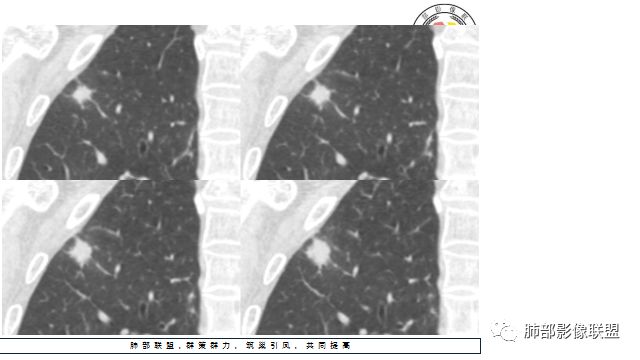

胸CT:右上肺结节,病灶位于胸膜下,边缘可见平直 u型征 软毛刺 晕,增强可见延迟强化,病灶中心低密度区。

2.右肺尖类圆形结节影,边界清楚,未见明显分叶或深切迹,部分分边缘较平直,可见细长毛刺棘状突起,相邻胸膜增厚,未见胸膜凹陷。后段胸膜下见条索影及微小结节影。

相关血管未见脐凹,有限图像层面未能显示相关支气管情况。

3.平扫病灶密度密度不甚均匀,外侧份见微小高密度影。

4.增强扫描成明显环形强化,中央液化坏死,内壁清楚且较为规整。